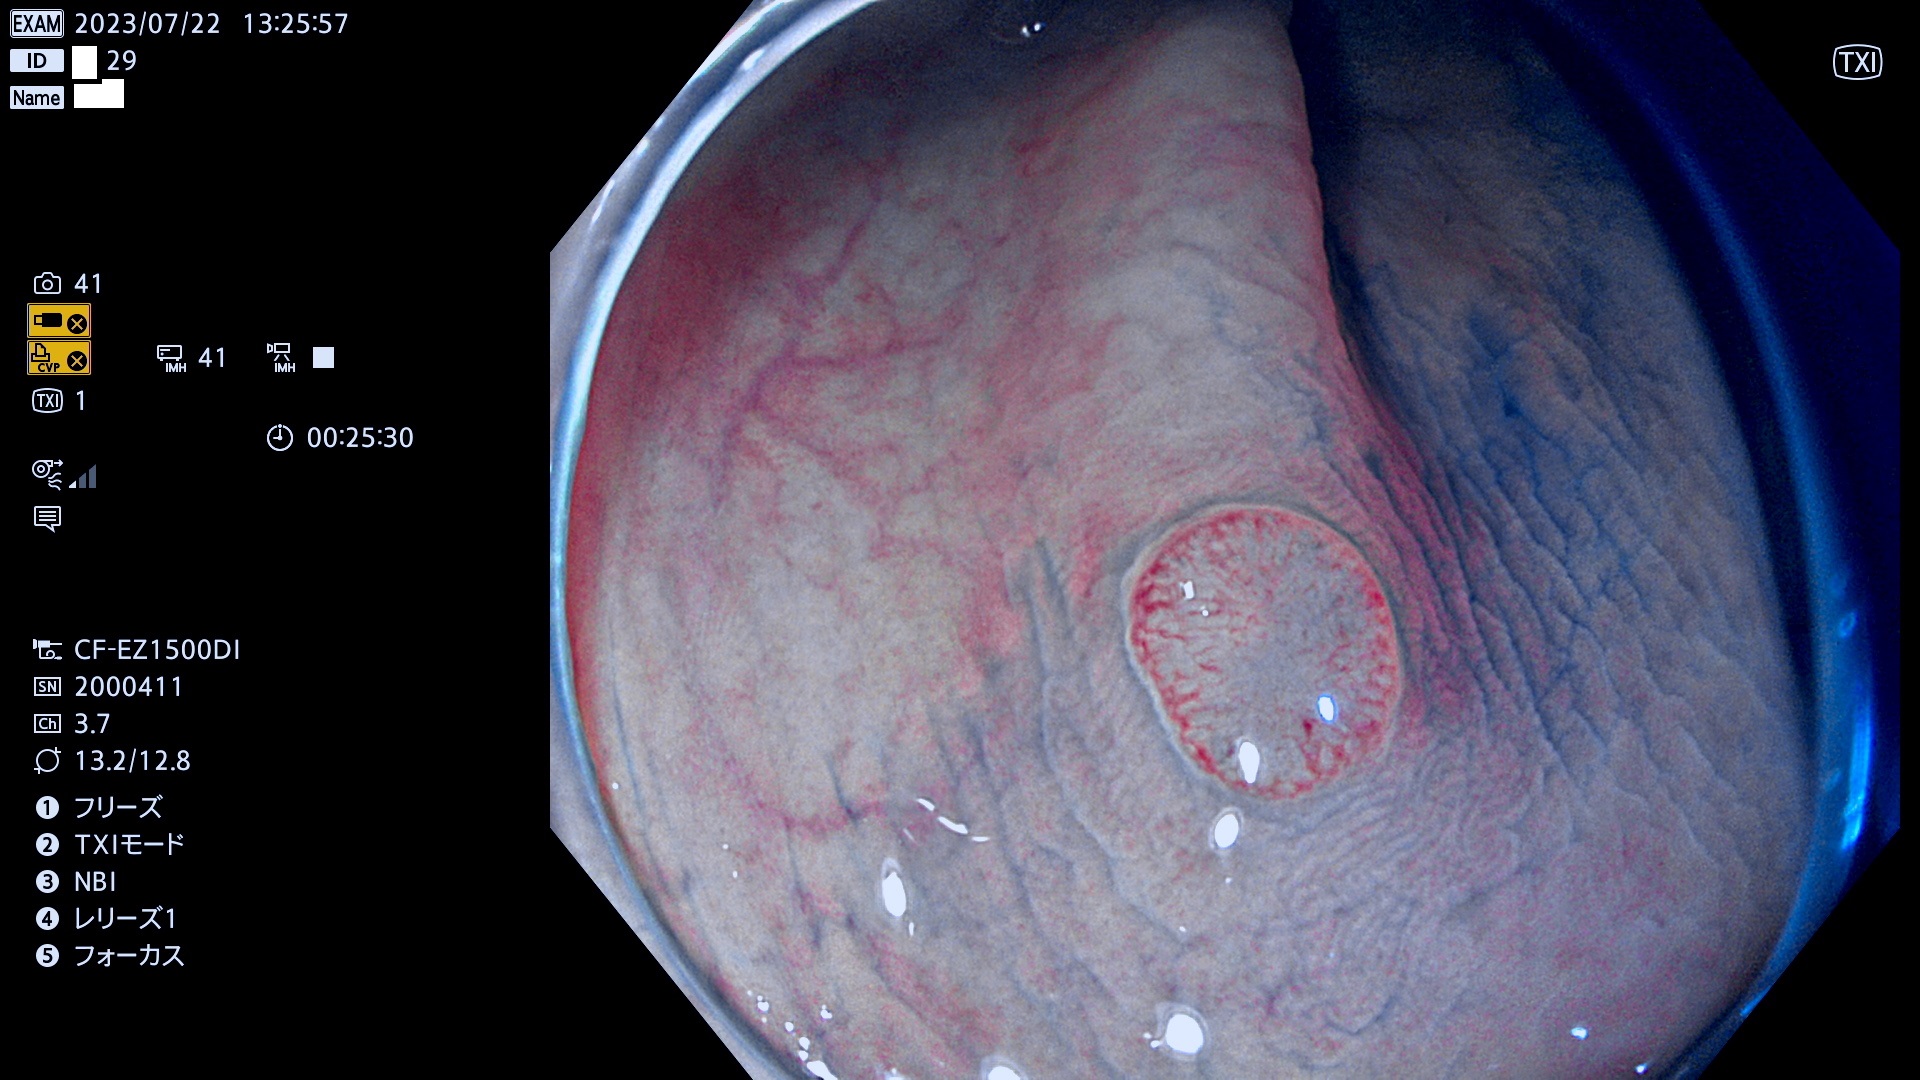

「表面型腺腫(Flat Adenoma)の中で、完全に平坦な物をUb、陥凹している物をUcと呼びます。平坦隆起型(Ua)よりも、発見が難しく危険な病変です。このタイプは「内視鏡後・大腸癌の重要犯人」であり、この発見率は「腺腫発見率」よりも、重要な意味があります。

毎週の検査(木・金・土・日)に発見されたUb、Uc型・腺腫を、その週の日曜の夜にUPし1週間、提示します。

抽出の対象期間 2023年7月20日(木)〜7月23(日)の4日間(48件の検査)12件